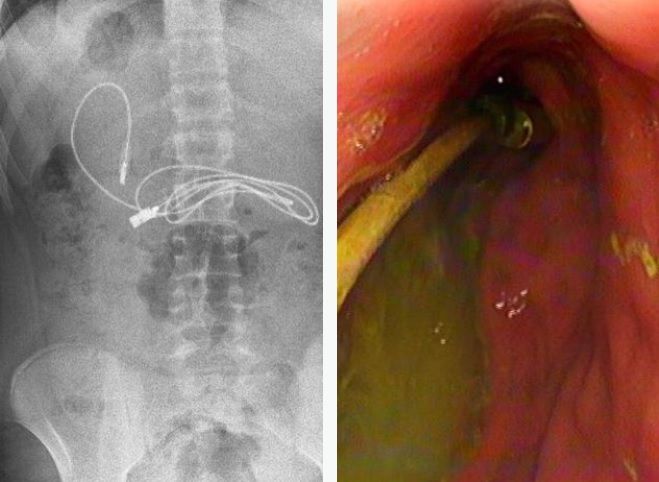

صدم مراهق الأطباء، بعد نقله إلى أحد مستشفيات تركيا وهو يعاني من غثيان شديد وآلام مبرحة في معدته، إذ أظهرت الأشعة المقطعية، ابتلاعه سلك شاحن طوله 90 صنتيمتراً.

وخضع المراهق الذي لم تكشف هويته، إلى عملية عاجلة لاستخراج السلك من معدته، ليتبين أنه ابتلع ربطة شعر، أيضاً، حسب صحيفة ميرور البريطانية.

وقال الطبيب الذي أشرف على الجراحة، إن العملية كانت معقدة لأن أحد طرفي السلك مَر إلى الأمعاء الدقيقة. ولحسن الحظ، تعافى المراهق، 15 عاماً، سريعاً بعد العملية وعاد إلى منزله في ديار بكر بصحة جيدة.